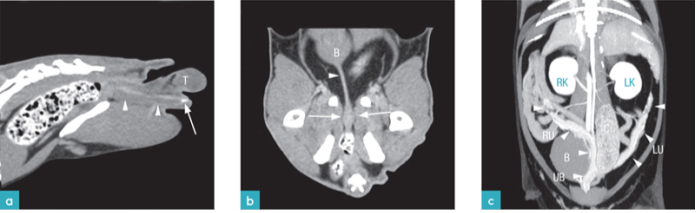

正常公猫的生殖系统包括:两个睾丸、两个附睾、两条输精管、前列腺、尿道球腺(库柏氏腺)、尿道以及阴茎。阴囊位于肛门和包皮之间,有两个囊腔,每个囊腔内都有一个睾丸和附睾及精索的末端。公猫的前列腺位于后腹部,靠近骨盆的入口。前列腺位于尿道的起始部及输精管的末端。尿道球腺在尿道的两侧。阴茎尖端(龟头)上覆盖有大约120-159个倒刺。这些倒刺在十二周龄时出现,青春期时得以完全发育。倒刺会在公猫去势后的第6周自然消失。91%以上的公猫具有阴茎骨,阴茎骨为3mm长、1.5mm宽的长圆形骨质组织(图1)。

母猫的生殖系统类似于狗。由2个卵巢和输卵管,子宫(子宫角,子宫体,子宫颈),阴道和外阴组成(图1)。

公猫有两个副性腺:前列腺和尿道球腺。前列腺由两部分构成:前列腺体部(前列腺外腺)位于骨盆尿道段头侧的周围;前列腺弥散部位于尿道粘结石(图3)。